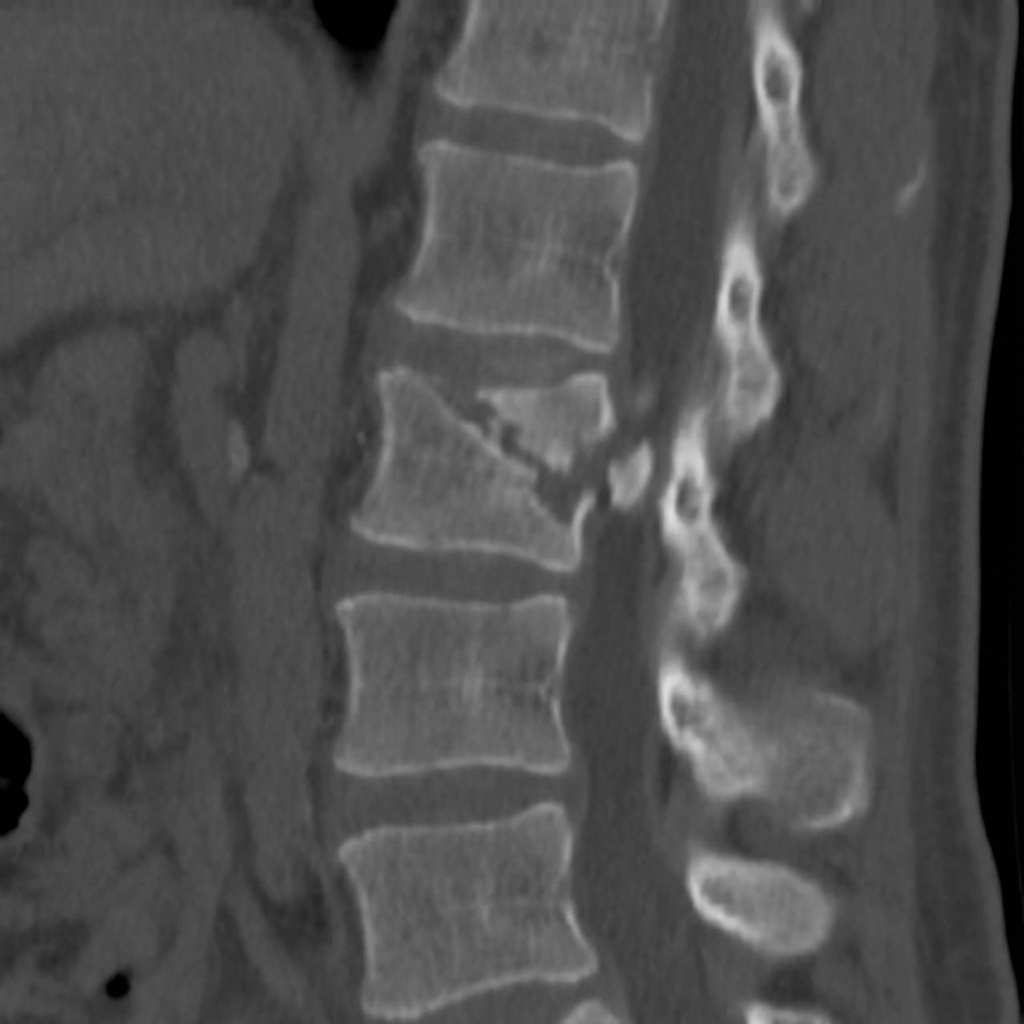

Sagittal and axial CT images demonstrating L1 burst fracture with loss of anterior vertebral body height, retropulsion of a posterior wall fragment causing 50% canal compromise, and widening of the interpedicular distance. The patient has an incomplete neurological deficit. This represents an unstable thoracolumbar junction injury requiring surgical stabilization.

Describe the CT findings and classify this injury using TLICS.